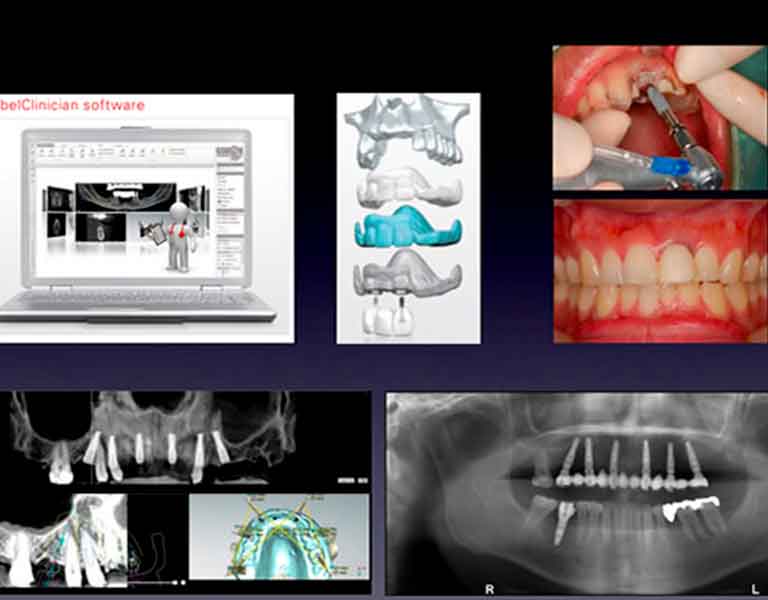

コンピュータガイド・インプラント治療システム

安全・確実なインプラント手術を可能に

ノーベルクリニシャンはインプラントの治療計画シミュレーションからインプラント手術までの一連のインプラント治療を、より安全に、より正確に行うことを目的に、ノーベルバイオケア社が開発した画期的なシステムです。

デジタルインプラント

「切らない。腫れない。その日に歯が入る。デジタルインプラントのすべて」インプラント治療のナビゲーションシステムと言えるシステムが「デジタルインプラント」です。